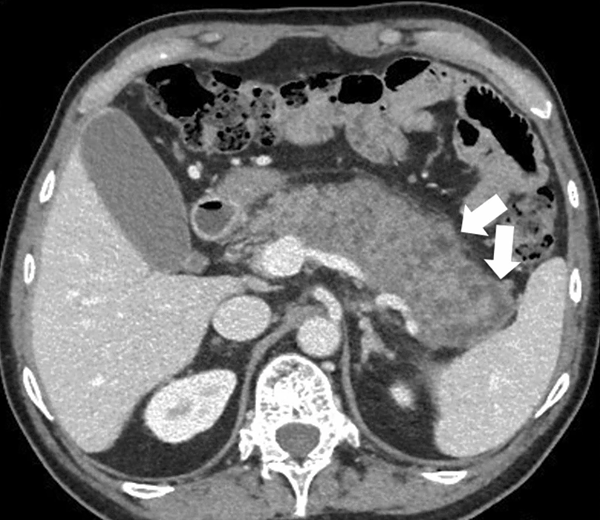

Внутричерепная гипотензия: КТ-исследования и их интерпретация

Раздел: Образы вокруг